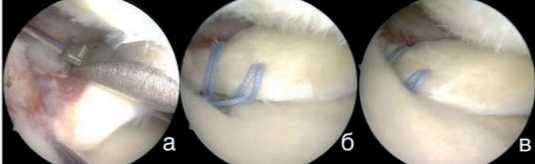

МРТ коленного сустава выполняли до операции и через 12 мес. после операции, оценивая экструзию прооперированного мениска в T2-режиме во фронтальной проекции от медиального края большеберцовой кости, не считая остеофит, до мениска в области его наибольшей его экструзии. (рис. 1) Данные исследования были выполнены на аппаратах мощностью не менее 1,5 Тесла. Экструзия мениска оценивалась одним специалистом по описанной выше методике.

Рисунок 1. МРТ коленного сустава пациента А. фронтальная проекция Т2 режим. Метод оценки уровня экструзии

Рисунок 6. Этапы фиксации корня мениска: а) прошивание корня медиального мениска при помощи инструмента Knee Scorpion; б) прошитый мениск, нити погружены в ранее сформированный канал и выведены на наружный кортикальный слой большеберцовой кости; в) вид медиального мениска после фиксации и натяжения нитей на кортикальной пуговице